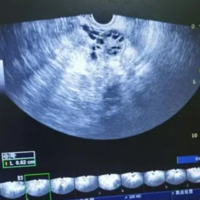

B超看到优势卵泡有分隔会影响排卵吗?

问题描述:我从去年就开始备孕了,但因为年底了工作上都比较忙碌所以就耽搁到年后再开始。因为我身体不是很好,所以医生建议我们做卵泡发育监测。昨天去检查的时候看到有优势卵泡存在,但医生说出现了分割的状况,我也不是很懂。就想知道这个情况会不会影响排卵?最佳回答:B超看到优势卵泡有分隔会影响排卵。但因为产生的原因有很多,因此优势卵泡能否排卵药取决于很多种情况。优势卵泡有分隔有生理性和病理性两种,若是生理性的...